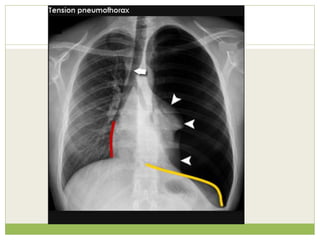

๏‚— In a minority of cases, the amount of air in the chest

increases markedly when a one-way valve is formed by

an area of damaged tissue, leading to a Tension

Pneumothorax.

๏‚— This condition is a medical emergency that can cause

steadily worsening oxygen shortage and low blood

pressure. Unless reversed by effective treatment, these

sequelae can progress and cause death.